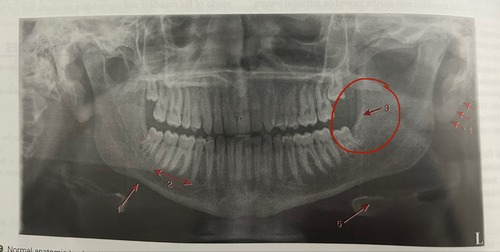

Maxillary sinus

maxillary tuberosity (3rd molar region)

External oblique ridge

Mental foramen

Submandibular fossa

Soft tissue of ear